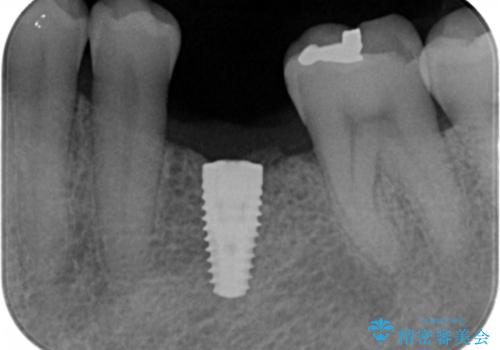

奥歯の欠損 インプラント治療

- 奥歯を失ったのち放置してしまった部位にインプラント治療を希望されて来院されました。

少量の骨造成を併用したインプラント治療を計画します。

インプラン治療は、ブリッジと異なり前後の歯を削る必要がなく、入れ歯と違い取り外しの必要がありません。